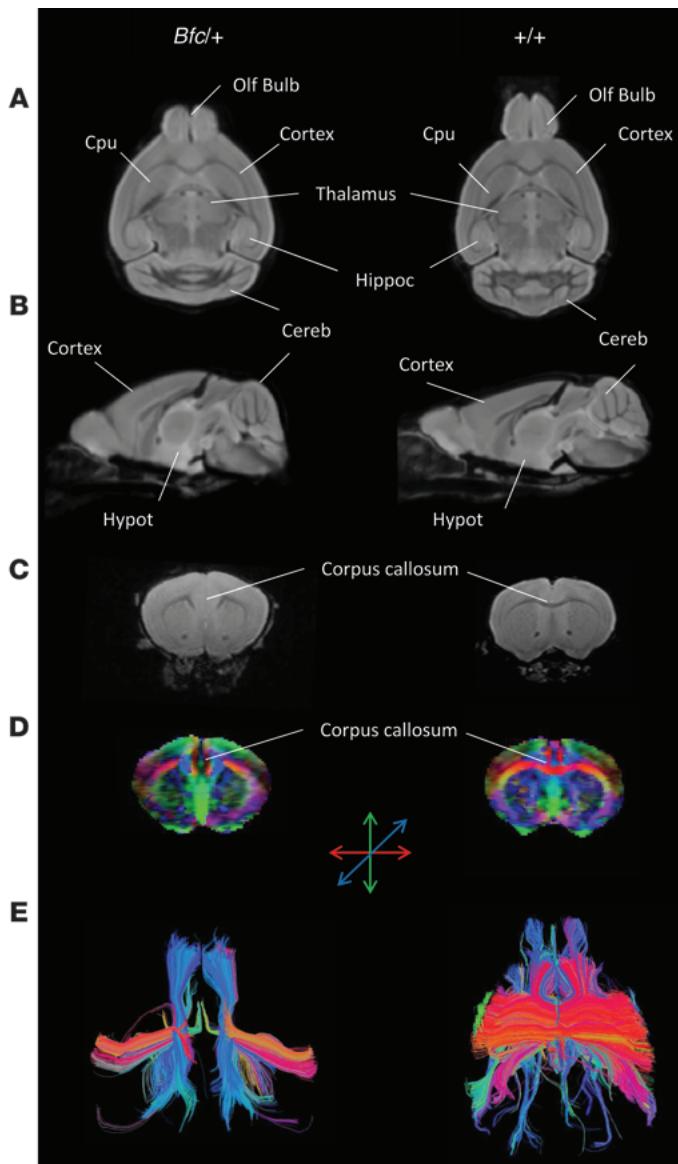

We proceeded to characterize Bfc at neuroanatomical and behavioral levels. Using MRI, we found a number of major abnormalities in mutants. The anteroposterior axis was significantly shortened, whereas the dorsoventral and medial-lateral axes were enlarged (Figure 3, A and B). In contrast to what was found in mice overexpressing -catenin (18), gyrification of the cerebral cortex was not observed. However, gray matter and total brain volumes were significantly larger in ; 1-way ANOVA, Supplemental Figure 5A). When normalized to brain volume, however, the relative gray matter and white matter content in was not statistically different from that of controls (Supplemental Figure 5B). Alterations in the absolute and relative volume of multiple anatomical brain structures were also found (Supplemental Figure 6). The thalamus, striatum, and globus pallidus were slightly, but significantly, larger in . However, mutants showed substantially reduced cerebellar and olfactory bulb volumes compared with WT. In addition to these general morphological features, the corpus callosum appeared to be severely underdeveloped in individuals, lacking any interhemispheric extensions (Figure 3, C–E). This was reminiscent of the human case with callosal hypoplasia described above. No evidence of major corpus callosum alterations was observed in the remaining brains or in the control group. Reductions in olfactory bulb, cerebellum size, and abnormal corpus callosum found with MRI were confirmed in histopathological sections of mouse brain (Supplemental Figure 7).

Figure 3 MRI scans of mice reveal major brain abnormalities. MRI scans of mice highlighted an altered cranial shape with a larger leftright axis and a shorter longitudinal extension compared with controls. The effect was apparent in horizontal (A) and sagital (B) views of the brain. The olfactory bulbs and cerebellum appeared to be significantly smaller in individuals compared with control littermates. In 3 out of subjects, the corpus callosum appeared to be severely underdeveloped, lacking any interhemispheric extension. This was apparent in anatomical T2-weighted images © as well as in diffusionweighted scans (D and E). Diffusion tensor images (DTI) modulated by FA (D) and DTI tractography corroborated the lack of interhemispheric connection of the corpus callosum in all of the 3 subjects, showing abnormal callosal anatomy in anatomical MRI images (C, D, and E show data from representative and control subjects). Normal interhemispheric tracts were observed in all the control subject images. Cereb, cerebellum; Cpu, caudate putamen; Olf Bulb, olfactory bulbs; Hippoc, hippocampus; Hypot, hypothalamus.